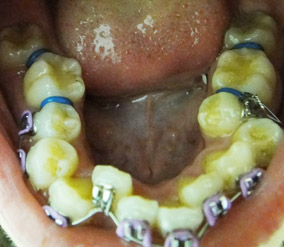

(10/3補上照片) 一星期後,也就是今天,我回診拿牙板。

又要開始戴下牙板的原因是我右邊咬合有問題,好像叫錯咬還是什麼我忘了,

醫生說我咬合後上排臼齒會比下排臼齒還靠內(好難形容…),所以要把我的上排往外拉,

因此牙板的功能是要我不要在拉牙齒時咬合,咬住的話就拉不出來了。